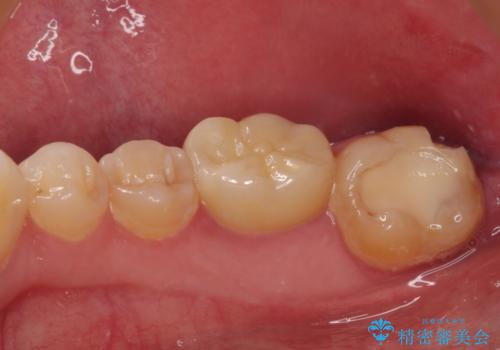

虫歯は歯髄組織のギリギリにまで及んでいたものの、歯髄組織が露出することはなく、処置から数日経った日に行った検査でも歯髄組織の異常所見は認めれらませんでした。

速やかに補綴治療を行い、無事に海外赴任前に治療を終えることができました。